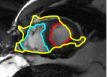

Figures 8 and 9 shows some sample tracking results of the proposed method and Medviso on full cardiac cycles of two different cases on both the LV dataset and the RV dataset. The ground truth (yellow) is superimposed when available. A summary of the results on the entire datasets is shown in Table I. The accuracy with respect to ground truth is measured using average perpendicular distance (APD) and dice metric (DM) for left ventricle, and Hausdorff distance (HD) and DM for the right ventricle. These metrics are chosen since they are the standard ones used on these datasets. Both qualitative and quantitative results show that our proposed method leads to more accurate segmentation of the ventricles and thus leads to less interaction than segmentation propagation schemes in than Medviso.

| initial | ventricle tracked (red - algorithm result, yellow - ground truth) | |||

|---|---|---|---|---|

|

Medviso |

||||

our method |

Medviso

![]() |

our method